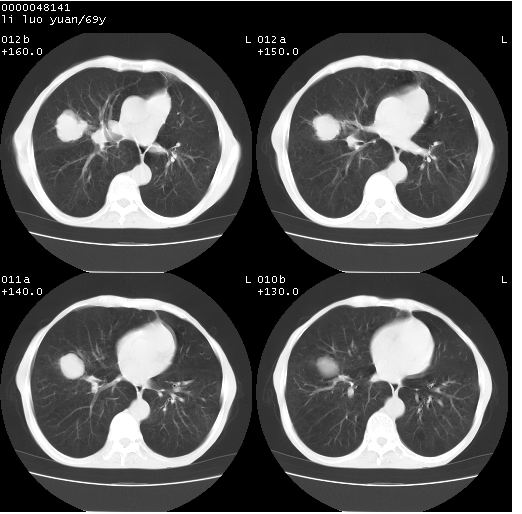

临床资料:老年患者,咯血、消瘦

影像表现:桶状胸,双肺纹理纤细、紊乱,透过度增高,肺野内可见多发、散在、大小不等的无壁高透过影,右肺中叶外侧段分叶样软组织占位,左上肺纤维索条样密度影,相应层面左侧胸腔轻度萎陷,纵隔左移。

影像诊断:1、慢支、肺气肿、双下肺野肺大泡形成

2、左上肺陈旧性肺结核

3、右肺中叶外侧段占位 考虑肺ca可能性较大、建议增强及痰检脱落细胞